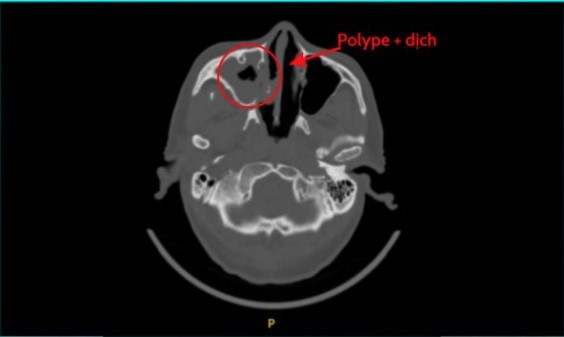

Hình ảnh CT của bệnh nhân viêm xoang nấm - Ảnh BVCC

Tại Khoa Liên Chuyên Khoa, ông được BS.CKI Trương Thùy Nga thăm khám và chỉ định nội soi mũi, chụp CT scan. Dưới hệ thống nội soi hiện đại, ekip bác sĩ phát hiện một bên mũi chảy nhiều dịch đục, toàn bộ xoang bị nấm bám kín. Một số cấu trúc xương đã bị chèn ép lâu ngày dẫn đến phá hủy, niêm mạc vách ngăn cũng loét do tì đè.

CT scanner ghi nhận xoang hàm, xoang sàng sàng và khe mũi giữa bên phải chứa đầy dịch mủ và ổ nấm. Trường hợp này, điều trị bằng thuốc hầu như không hiệu quả, phẫu thuật nội soi mũi xoang là giải pháp tối ưu để loại bỏ hoàn toàn ổ nấm.